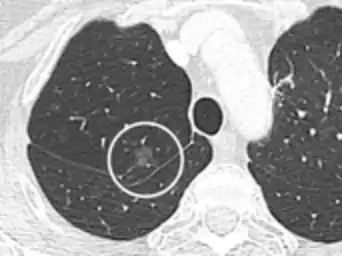

- CT image showing ground-glass nodule (circled).

Nodular

There are numerous potential causes of nodular GGOs which can be broadly separated into benign and malignant conditions. Benign conditions potentially leading to the formation of nodular GGOs include aspergillosis, acute eosinophilic pneumonia, focal interstitial fibrosis, granulomatosis with polyangiitis, IgA vasculitis, organizing pneumonia, pulmonary contusion, pulmonary cryptococcus, and thoracic endometriosis. Focal interstitial fibrosis presents a unique challenge when differentiating from malignant nodular GGOs on CT imaging. It is typically persistent over long-term imaging follow-up and shares a similar appearance to malignant nodular GGOs.[9]

Pre-malignant or malignant causes of nodular GGOs include adenocarcinoma, adenocarcinoma in situ, and atypical adenomatous hyperplasia (AAH). One large review study found that 80% of nodular GGOs which were present on repeated CT imaging represented either pre-malignant or malignant growths. Differentiating between pre-malignancy and malignancy on the basis of CT alone can pose a challenge to radiologists; however, there are several features that are indicative of pre-malignant nodules. AAH is a pre-malignant cause of nodular GGO and is more commonly associated with lower attenuation on CT and smaller nodule size (<10 mm) compared to adenocarcinoma.[10] In addition, AAH often lacks the solid features and spiculated appearance that are often associated with malignant growths.[9] In contrast, as adenocarcinoma becomes invasive it will more often cause retraction of adjacent pleura and may show an increase in vascular markings. Nodules >15 mm almost always represent an invasive adenocarcinoma.[9][10]